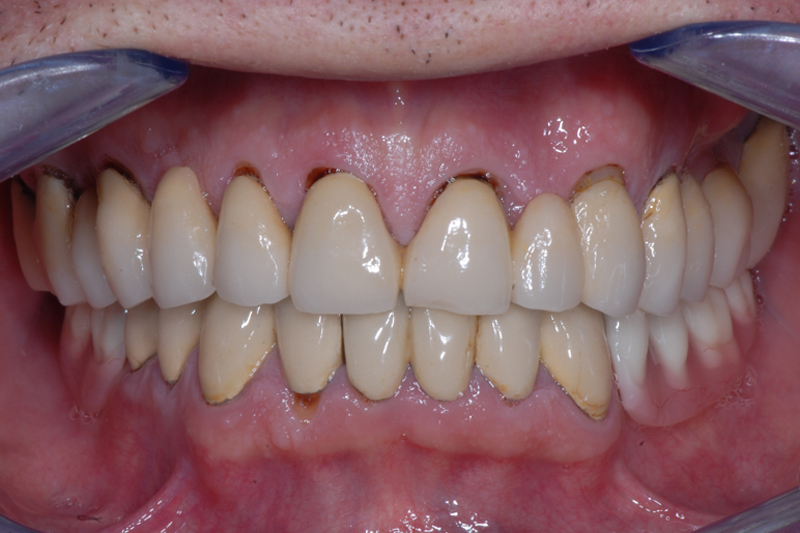

- Status kliniczny przed rozpoczęciem terapii – widok frontalny zębów w zgryzie